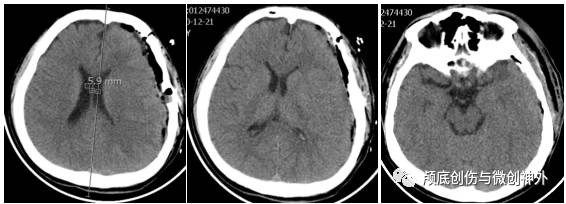

头颅CT:

1.左侧额颞颞亚急性硬膜下血肿;

2.颅内高压。

3. 影像学提示:中线移位大于1cm,左侧颞叶沟回压迫脑干,左侧顶部皮层脑沟变窄,脑回增宽,回流静脉曲张。

术后复查CT: